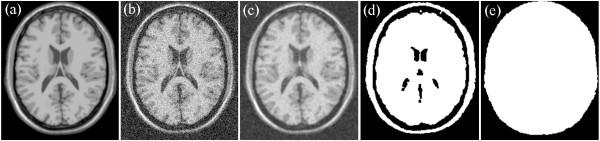

Considering the characteristics of both Rician noise and the NLM filter, this study proposes a frame for a pre-smoothing NLM (PSNLM) filter combined with image transformation. In the PSNLM frame, noisy MRI is first transformed into an image in which noise can be treated as additive noise. Second, the transformed MRI is pre-smoothed via a traditional denoising method. Third, the NLM filter is applied to the transformed MRI, with weights that are computed from the pre-smoothed image. Finally, inverse transformation is performed on the denoised MRI to obtain the denoising results.

To test the performance of the proposed method, both simulated and real patient data are used, and various pre-smoothing (Gaussian, median, and anisotropic filters) and image transformation [squared magnitude of the MRI, and forward and inverse variance-stabilizing trans-formations (VST)] methods are used to reduce noise. The performance of the proposed method is evaluated through visual inspection and quantitative comparison of the peak signal-to-noise ratio of the simulated data. The real data include Alzheimer's disease patients and normal controls. For the real patient data, the performance of the proposed method is evaluated by detecting atrophy regions in the hippocampus and the parahippocampal gyrus.

The comparison of the experimental results demonstrates that using a Gaussian pre-smoothing filter and VST produce the best results for the peak signal-to-noise ratio (PSNR) and atrophy detection.